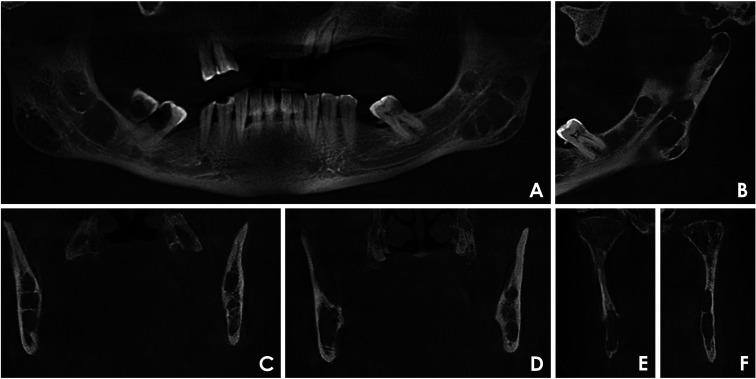

目的:本研究分析了27例多发性骨髓瘤患者在不同疾病阶段的锥形束计算机断层图像,以确定颌骨破坏模式并评估其与临床数据的关系。材料和方法:在这项横断面研究中,2名训练有素的审查员进行了标准化的、基于共识的图像分析。病变分为4种不同的骨破坏模式:弥漫性、多房性、单房性和穿孔性。临床数据从医疗记录中收集。结果:本组患者男性占51.8%,女性占48.2%,年龄以42 ~ 60岁为主。所有病例均表现为双颌弥漫性骨破坏。多房型和单房型分别占51.9%和29.6%,未发现穿孔病变。单眼模式与国际分期系统I期和Durie-Salmon期IIIA期的病例有显著相关性。结论:在研究的多发性骨髓瘤病例中,最常见的骨破坏类型是弥漫性和多房性。没有穿孔病变可能是由于使用了三维成像。在单眼模式和疾病分期之间确定了明确的关联。

Purpose: This study analyzed cone-beam computed tomography images of 27 patients with multiple myeloma at different disease stages to identify jawbone destruction patterns and assess their associations with clinical data.

Materials and methods: In this cross-sectional study, 2 trained examiners performed standardized, consensus-based image analyses. Lesions were classified into 4 distinct bone destruction patterns: diffuse, multilocular, unilocular, and punched-out. Clinical data were collected from medical records.

Results: The sample included 51.8% male and 48.2% female patients, predominantly between 42 and 60 years old. All cases exhibited diffuse bone destruction affecting both jaws. Multilocular and unilocular patterns were observed in 51.9% and 29.6% of cases, respectively, while no punched-out lesions were identified. The unilocular pattern was significantly associated with cases classified as International Staging System stage I and Durie-Salmon stage IIIA.

Conclusion: Among the studied cases of multiple myeloma, the most frequently observed bone destruction patterns were diffuse and multilocular. The absence of punched-out lesions may be attributable to the use of 3-dimensional imaging. A clear association was identified between the unilocular pattern and disease staging.